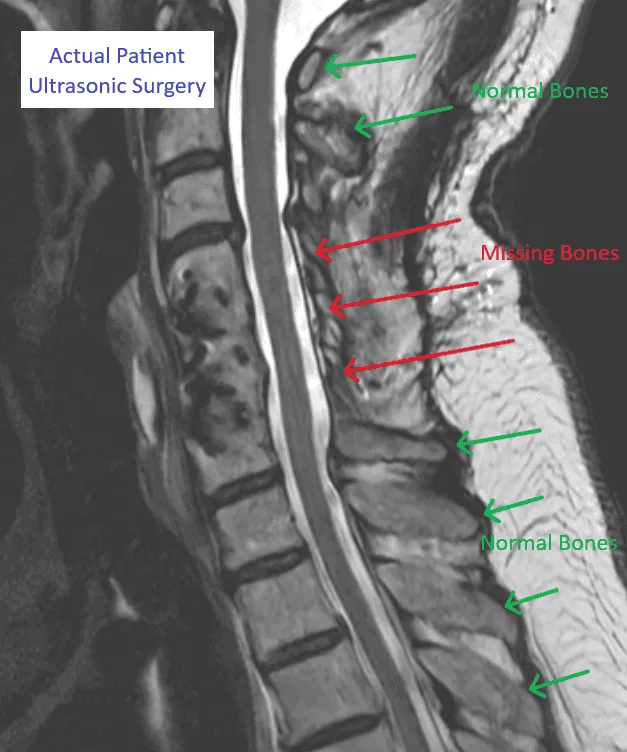

MRI image of a spine showing areas with normal and missing bones labeled in green and red.

Destruction of Stabilizing Bones

Medical scan showing normal and missing spinal bones with herniated disc, labeled for ultrasonic surgery.

Pain Source NOT Treated